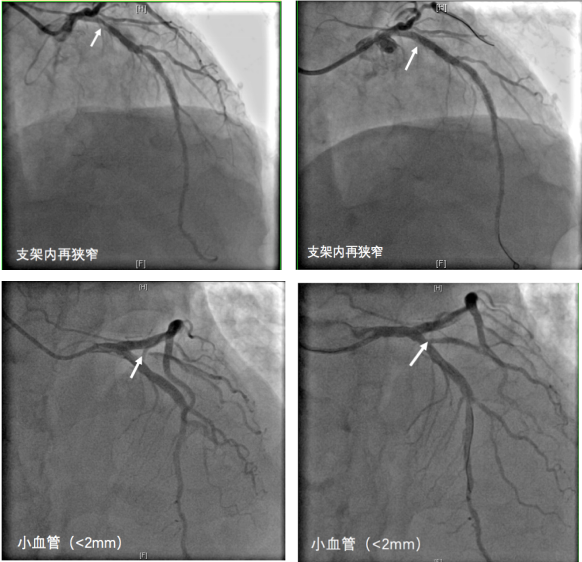

药物球囊可以替代支架吗?目前药物球囊主要应用于支架内再次狭窄病变、血管直径较小的病变(<2mm)、血管分叉病变治疗。使用支架还是药物球囊,这要根据个人的病情来决定,介入专业医生会严格把握适应症,根据病情作出合理的选择。